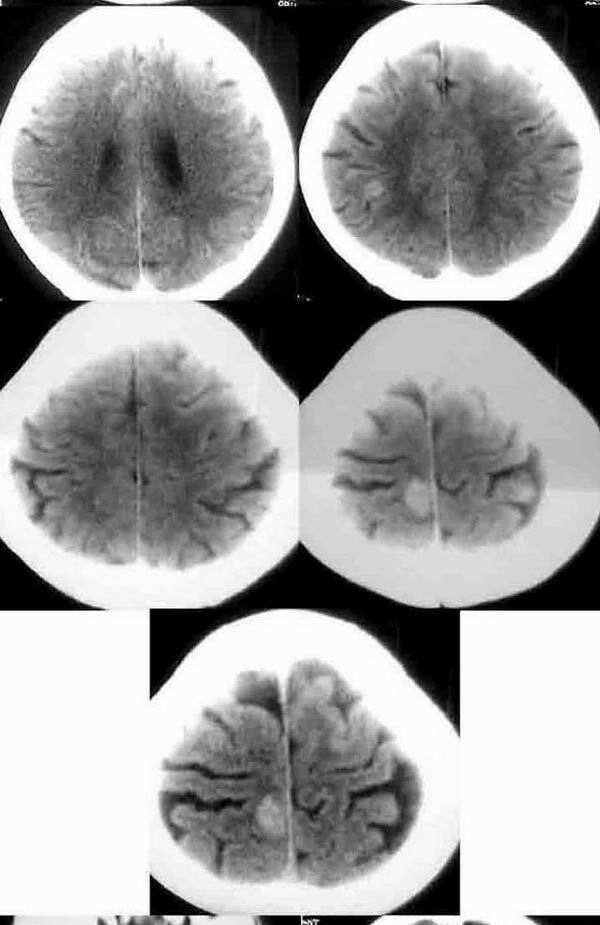

幕上幕下皮质及皮质下区多发散在等密度结节病灶,无水肿及占位,明显强化。

首先考虑多发肉芽肿

建议结合临床资料,不能单一ct影象表现。

本例皮层及皮髓交界处的多发等高密度无水肿结节,考虑脑转移瘤可能性更大一些。

因为无水肿,而区别于结核肉芽肿,部分肺及骨的恶性肿瘤脑转移灶可无水肿,而无水肿的结核肉芽肿更少;结核肉芽肿多位于脑浅表部位,皮髓交界处很少见,而脑转移瘤更多位于此处(分水岭);结核肉芽肿平扫密度应更一致而非此例为等密度及稍高密度,增强扫描多为环形、结节形或不均匀强化,而非此例均匀性强化;结核性肉芽肿多伴有脑积水、脑梗塞,脑底池往往有较特征性的强化。